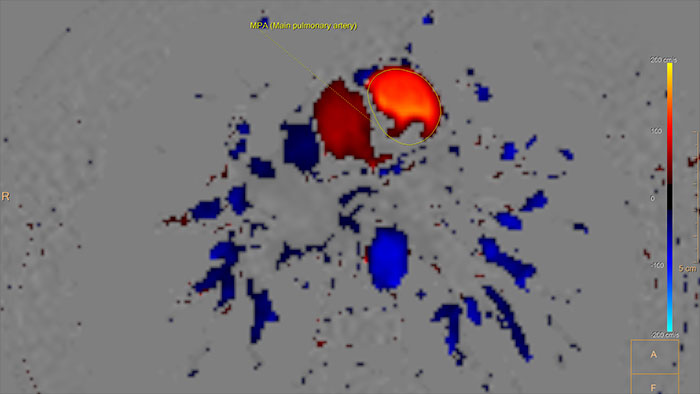

- QFlow

MR QFlow

Visualizing and quantifying blood flow dynamics

Supports visualization and quantification of blood flow dynamics by assisting in review of MR phase-contrast data, on vascular region of interest segmented manually, or semi-automatically. Qflow analysis is integrated as part of MR Cardiac Suite allowing flow and functional analysis in one suite with combined reporting.

Benefits

- Quantification includes the following parameters: stroke volume, regurgitant fraction, forward and backward flow volumes, flux, stroke distance, mean velocity, maximum velocity, minimum velocity, peak velocity, vessel area, peak pressure gradient, E/A ratio and deceleration time.

- The application supports manual background Correction (BC) to correct for phase (velocity) offset.